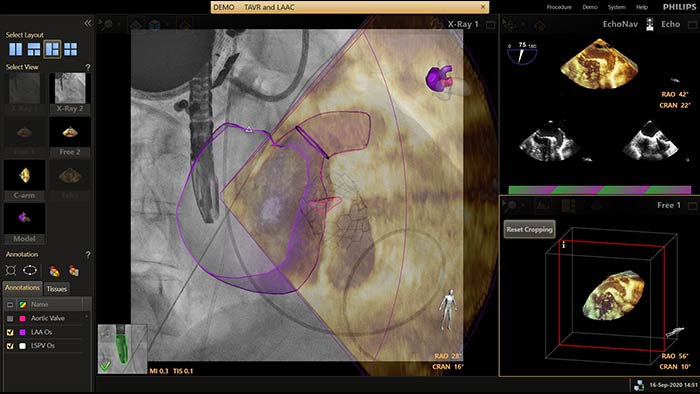

EchoNavigator reorienta y combina la información de ecografía y rayos X en una sola visualización aumentada para guiar y evaluar la relación dispositivo-tejido. En la oclusión de la orejuela izquierda (Left Atrial Appendage, LAA), EchoNavigator permite lo siguiente para aumentar la confianza y la eficiencia:

Soluciones para los procedimientos TAVR y TAVI que ofrece la terapia guiada por imágenes de Philips.